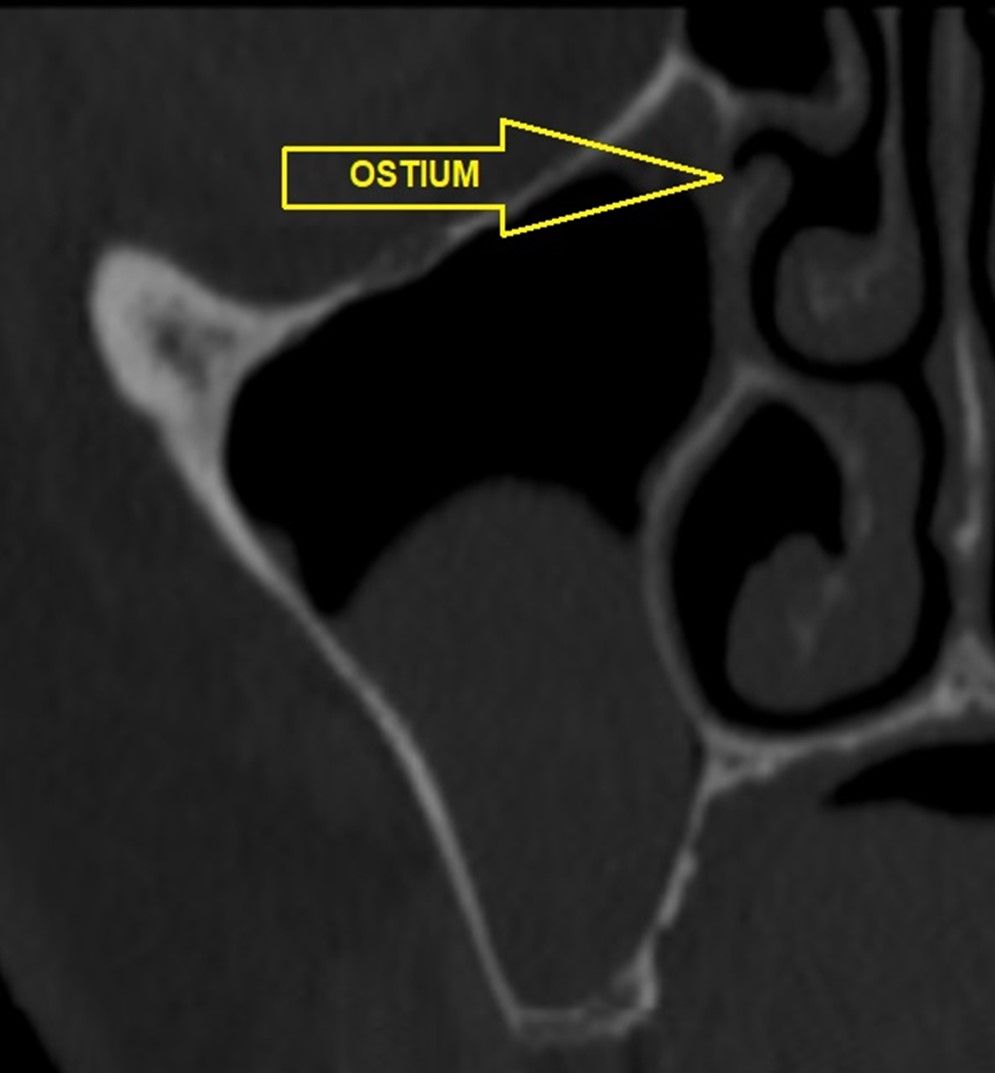

En la exploración radiográfica mediante escáner se apreció una lesión apical de pequeño tamaño en el 1.4 y una escasa disponibilidad ósea. Además, se observó imagen radioopaca cupuliforme de 3 x 2,8 cm en el seno maxilar derecho, compatible con un pseudoquiste sinusal (Figura 2). La extensión craneal alcanzaba la mitad superior del seno maxilar y el volumen de la lesión (5 cm³) era aproximadamente ⅓ del volumen sinusal (Figuras 3 y 4).

El tratamiento de la sinusitis crónica se realiza mediante corticoides nasales. En caso de que la patología crónica o aguda sea recurrente o no responda al tratamiento médico convencional, podrá requerir tratamiento quirúrgico para restablecer la función mucociliar normal, lograr la limpieza de los senos paranasales, la permeabilidad del ostium del seno maxilar y eliminación del exceso de tejido en el meato medio. Los tratamientos quirúrgicos más utilizados son la técnica de Caldwell-Luc, con abordaje a través de la fosa canina, y la cirugía endoscópica de los senos nasales, con abordaje a través de la fosa nasal23-25.